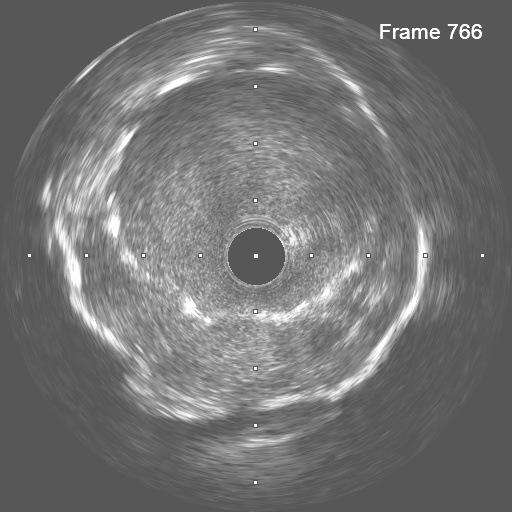

In anticipation of a high thrombus burden, intracoronary Tirofiban was given to mitigate thrombotic risks. The Terumo 6 Fr in 5 Glidesheath Slender was exchanged for a 7 Fr in 6 Glidesheath Slender to accommodate larger catheters while preserving radial artery access. Using a 7 Fr SAL 1.0 guiding catheter (Medtronic, USA), the Fielder FC 0.014” × 180 cm wire (ASAHI Intecc, Japan) was advanced to the distal RCA. Despite GuideLiner (Teleflex, USA) support, the Terumo Eliminate aspiration catheter could not advance beyond the mid-RCA. StentBoost imaging revealed the wire had wound along the aneurysmal vessel wall and passing through a previous stent’s strut. Attempts to reshape the wire tip for re-entry into the stent center were unsuccessful. Although stent crushing was considered, navigating the wire through the stent without damage was prioritized. An Euphora balloon (2.0 × 20 mm) was inflated at 2 atm to seal the gap between the stent and vessel wall, enabling the passage of a Runthrough NS Floppy wire into the distal RCA. IVUS confirmed the wire’s position within the stent, which remained intact. The wire was exchanged for an ASAHI Sion Blue Extra-support wire with a Caravel microcatheter. Thrombus aspiration was completed using the Eliminate catheter. Post-dilatation was performed with a Conqueror NC balloon (4.00 × 20 mm, APT Medical), followed by NC Emerge and Accuforce balloons (4.5-6.0 mm). IVUS confirmed excellent stent apposition, and TIMI 3 flow was achieved.

Case Summary

This case highlights the challenges of managing stents in STEMI patients with aneurysmal vessels. In such patients, vessel size is often underestimated during urgent procedures, leading to stent malapposition and an increased risk of thrombosis. IVUS or OCT is crucial for accurate vessel sizing and ensuring proper stent expansion. The gap between the stent and the vessel wall often causes the guidewire to preferentially pass through the aneurysmal vessel along the greater curve, rather than properly navigating through the stent. Finally, sealing these gaps with a small balloon facilitates guidewire passage and improves outcomes.